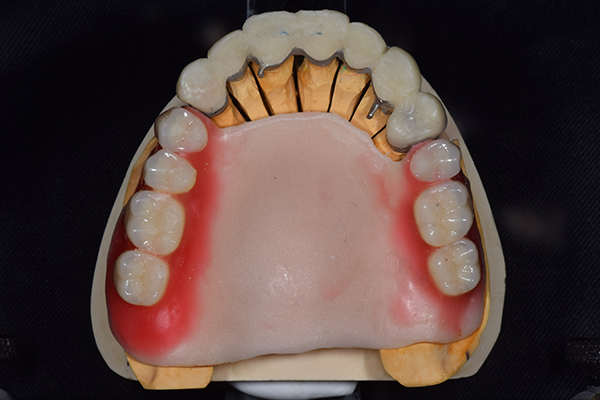

右上と左下の歯がない方です。 上の入れ歯の安定が悪く、作り直したいとのことでいらっしゃいました。 今お使いの上の入れ歯を見てみると、口蓋部分が抜けており、安定性に欠ける構造になっていました。この入れ歯はノンメタルクラスプデンチャーといって、金属のバネを使用しない 入れ歯になります。これは見た目は良いのですが、歯への負担が大きいことと、入れ歯自体がやわらかいため、噛むには不便なことがあります。

入れ歯は極力薄くするために金属を使用しました。しっかり噛める様にするため、ノンメタルクラスプデンチャーにはしませんでした。

上の入れ歯(表)

上の入れ歯(裏)

下の入れ歯